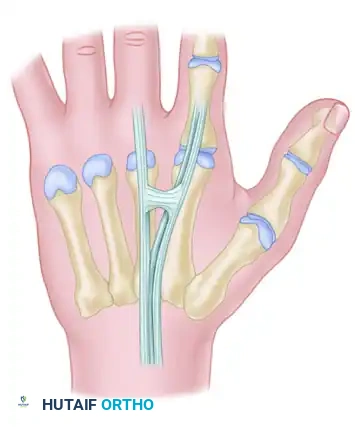

Additional anatomical variations and interconnections of the dorsal extensor mechanism are illustrated below, highlighting the complexity surgeons must navigate during dorsal hand reconstruction:

The Juncturae Tendinum

The juncturae tendinum are intertendinous connections located proximal to the metacarpophalangeal (MCP) joints. They serve a vital biomechanical role by coordinating digital extension and distributing forces across the dorsal hand. However, they also act as a double-edged sword in trauma, as they can mask complete tendon lacerations.

The juncturae are classified into three primary types based on their morphology and location:

Type 1 (Thin Filamentous Type):

Found predominantly between the EDC tendons of the long (EDC m) and index (EDC i) fingers. Notably, these juncturae do not connect to the EIP tendon. They are present in the second and third intermetacarpal spaces.

Type 2 (Thicker Type):

These are thicker, more robust connections found between the EDC tendons of the ring (EDC r) and long (EDC m) fingers. They are located exclusively in the third and fourth intermetacarpal spaces.

Type 3 (Subtype y):

In this variation, a Y-shaped tendon and juncturae appear as a split tendon inserting into two adjacent digits. This is most commonly seen between the EDC tendons of the ring (EDC r) and long (EDC m) fingers.

Type 3 (Subtype r):

This is a more oblique, R-shaped junctura between the EDC to the ring finger (EDC r) and the most radial of the three EDQ tendons to the small finger.